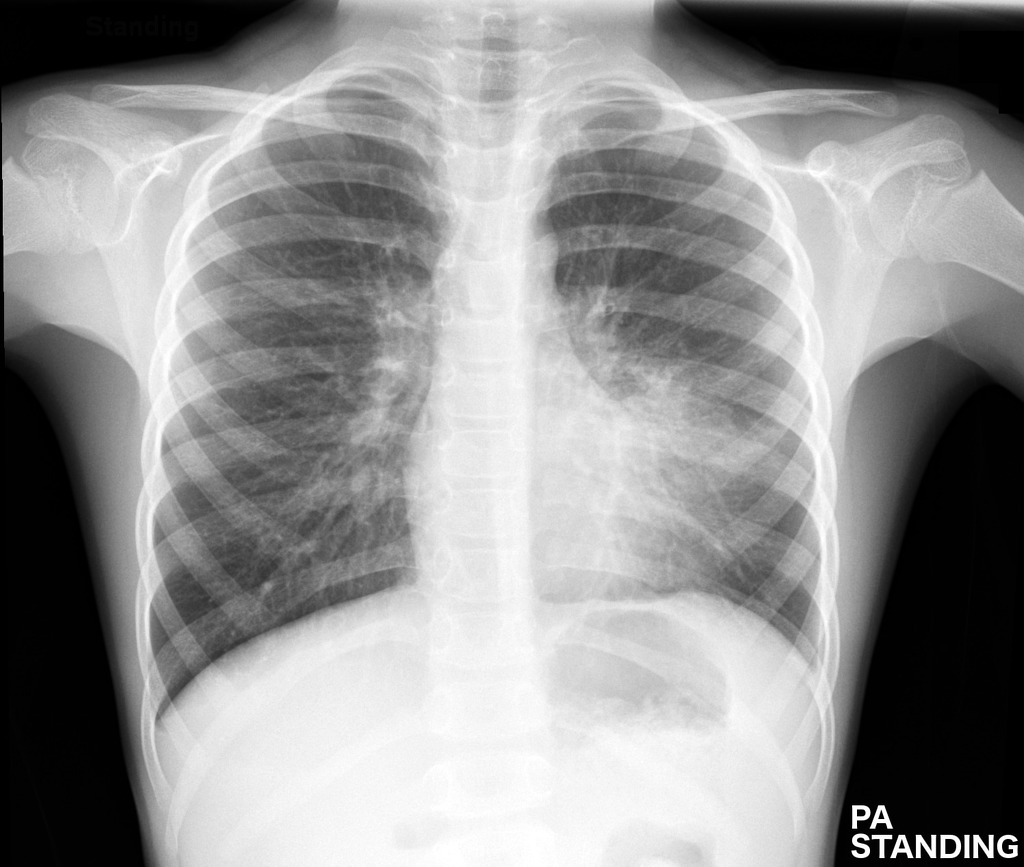

What Does A Chest X Ray Look Like With Pneumonia . Blood tests , such as a complete blood count (cbc) see whether. Dense, patchy infiltrates or areas of opacity within the lung tissue. if you go to a health professional or the emergency room with chest pain, a chest injury or shortness of breath, you will typically get a chest x. pneumonia ranks 8th as a cause of death in the usa and is the most deadly of the infectious diseases.